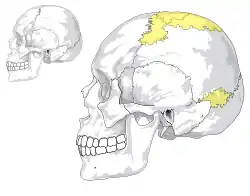

The following are images from various Medicine-related articles on Wikipedia.